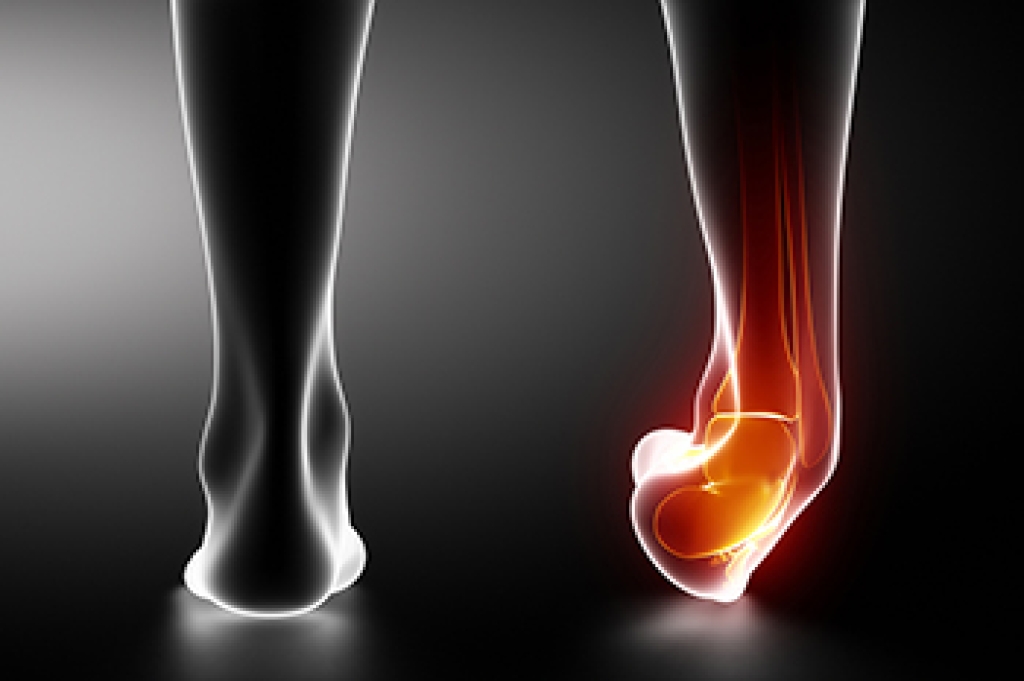

Recurrent ankle sprains often occur when the ligaments that support the ankle become weakened or overstretched from previous injuries. Each sprain can stretch these ligaments further, reducing stability and making the ankle more prone to rolling inward or outward during activity. The most frequently affected ligament is the anterior talofibular ligament, which helps keep the ankle from turning excessively. Symptoms of recurring ankle sprains include pain, swelling, tenderness, and a sense that the ankle gives way. Chronic ankle instability can develop if the ligaments and surrounding muscles lose their ability to properly stabilize the joint. A podiatrist can assess the degree of ligament damage and evaluate ankle alignment through physical examination and imaging. In some cases, surgery may be required to restore ligament strength and joint stability. If you have repeatedly sprained an ankle, it is suggested that you schedule an appointment with a podiatrist for a diagnosis and appropriate treatment options.

How Does an Ankle Sprain Occur?

Ankle sprains are the result of a tear in the ligaments within the ankle. These injuries may happen when you make a rapid shifting movement while your foot is planted. A less common way to sprain your ankle is when your ankle rolls inward while your foot turns outward.